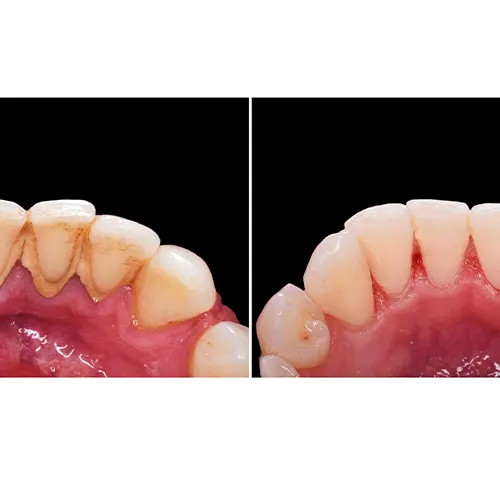

خونریزی و التهاب لثه (ژنژیویت)

تجمع پلاک و جرم در نزدیکی خط لثه، باعث تحریک و التهاب لثه می‌شود. این وضعیت که “ژنژیویت” نامیده می‌شود، معمولاً با علائمی چون قرمز شدن لثه‌ها، تورم و خونریزی هنگام مسواک زدن یا نخ دندان کشیدن همراه است. اگر ژنژیویت درمان نشود، می‌تواند به مراحل پیشرفته‌تر بیماری لثه (پریودنتیت) تبدیل شود.

۴. پولیش دندان: سطحی صاف و درخشان